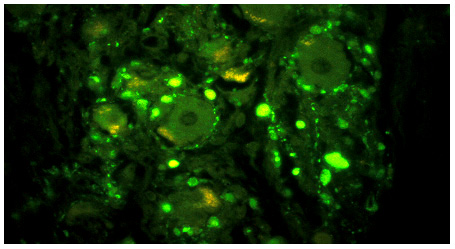

8A1,2 By a happy accident we examined immunohistochemistry for neuropeptide Y (NPY) which we did not expect in the sympathetic intraganglionic nerve terminals. (NPY IHC)